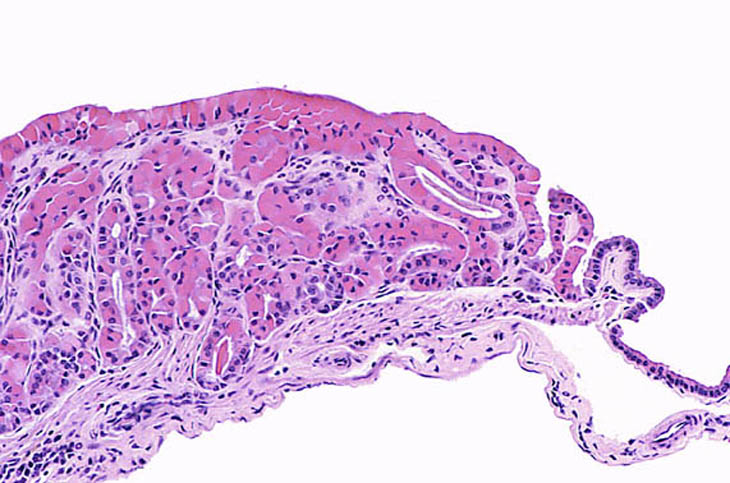

Eosinophilic crystalline inclusions and hyalin degeneration of epithelial cytoplasm in an adenomatous hyperplasia of the gallbladder. High magnification shows the brightly eosinophilic hyalinized cytoplasm of the epithelial cells.